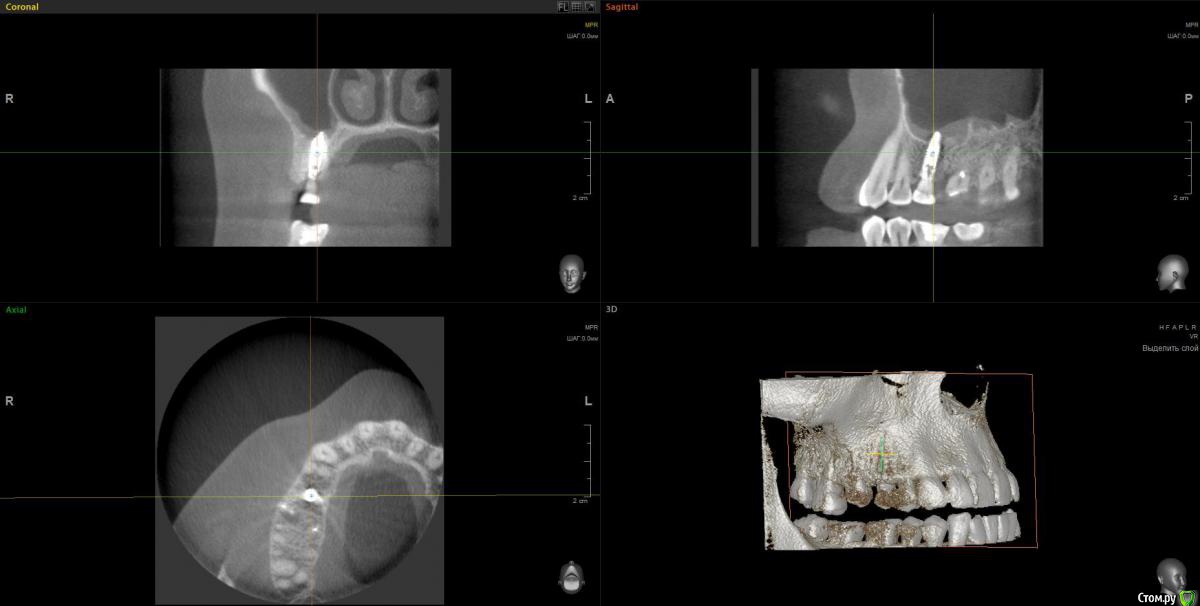

anvladd Опубликовано 31 января, 2017 Поделиться Опубликовано 31 января, 2017 (изменено) Как с носом, не гайморит ли ? 3 d бы глянуть, хотя бы этот сегмент. Изменено 31 января, 2017 пользователем anvladd Ссылка на комментарий

Весна2009 Опубликовано 31 января, 2017 Автор Поделиться Опубликовано 31 января, 2017 Вы тоже думаете, что имплант в гайморовой? Ссылка на комментарий

wladdX Опубликовано 2 февраля, 2017 Поделиться Опубликовано 2 февраля, 2017 Несколько скриншотов на скорую руку. Ссылка на комментарий

Весна2009 Опубликовано 2 февраля, 2017 Автор Поделиться Опубликовано 2 февраля, 2017 Несколько скриншотов на скорую руку.Огромное Вам спасибо! Может быть, есть желающие прокомментировать снимки? Заранее спасибо Ссылка на комментарий